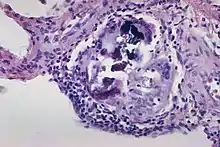

Fritz Heinrich Jakob Lewy, a German-American neurologist, first identified and described inclusions in the brain cells of patients with Parkinson’s disease and published his findings in the Lewandowsky’s Handbook of Neurology in 1912.[3] I-cells also called inclusion cells are abnormal fibroblasts having a large number of dark inclusions in the cytoplasm of the cell (mainly in the central area). They are metabolically inactive structures of a cell and are not enclosed by a membrane.[4] The inclusions are of various fats, proteins, carbohydrates, pigments, excretory products, crystals,[5] and other insolubles. They are found in the cytoplasm of a cell in both prokaryotes and eukaryotes.[6] They are seen in Mucolipidosis II,[7] and Mucolipidosis III, also called inclusion-cell or I-cell disease where lysosomal enzyme transport and storage is affected.[8]

- USA, Yale Rosen from (2011-08-04), The crystalline inclusions that may be found within the giant cells in sarcoidosis and other granulomatous disorders consist mainly of calcium oxalate and well as some calcium cargbonate. In this image there are multiple Schaumann bodies closely associated with crystalline inclusions. In many cases the crystals appear to serve as a nidus around which Schaumann bodies are formed. H&E stain., retrieved 2021-12-10